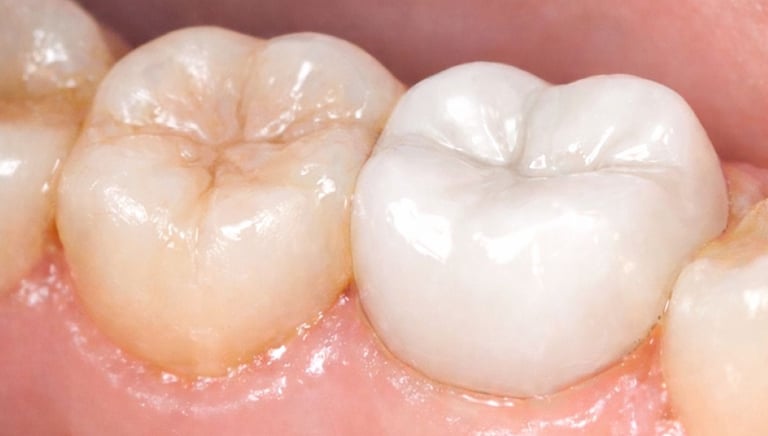

Tooth Colored Filling in Shyamal, Ahmedabad

Tooth-colored fillings are used to restore decayed or broken teeth while maintaining a natural appearance. These fillings blend seamlessly with your tooth color and help preserve your smile.

All images shown here are real tooth colored filling cases treated at our clinic with patient consent.

At Shree Dental Care, cosmetic fillings are placed carefully with a focus on comfort, precision and long-term durability. We ensure minimal tooth cutting and natural-looking results.

If you are looking for aesthetic tooth colored filling in Shyamal, Ahmedabad, you can book an appointment with our clinic.